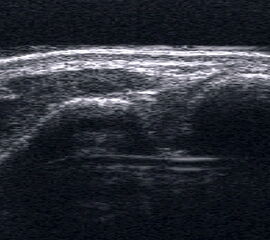

Echogene Verdickung im Subkutangewebe bei Lymphödem

Abbildung 8

Lagerung: Rückenlage.

Schnittebene: Ventraler LS über dem OSG.

Referenzstrukturen: Distale Tibia und Talusrolle, darüber Gelenkkapsel. Befunde: Echogene Verdickung subkutan (Abb. 8), hier peronäal oberhalb des OSG. Bei Varicosis sind in der Subkutis erweiterte Venenkomplexe mit echoarmem Lumen und positivem Doppler-Signal zu sehen.